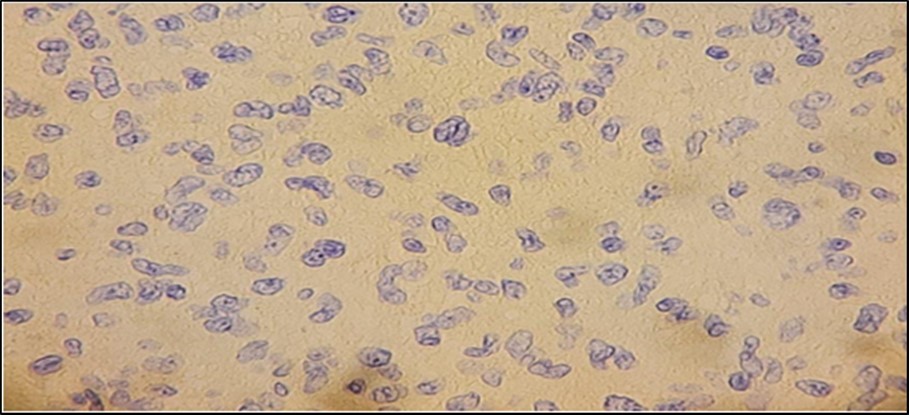

We have a case whose diagnosis needs to be confirmed. The previous biopsy showed histopathology consistent with a neurofibroma, with monomorphic, spindle-shaped, distinct cells, well-spaced, with scant mitosis. Neurofibromas are an autosomal dominant hereditary disease with a varied phenotype that affects the skin and nervous system. Affectation is one out of every 3,500 live births throughout the world. A spontaneous mutation on chromosome 17 is thought to be responsible for around half of the cases7. Figure 3. Comparison between biopsies taken five months apart. The histopathology in the biopsy done in February shows well-spaced uniform cells (black arrows). The biopsy done in July shows cellular congestion with atypical, pleomorphic cells with increased mitotic activity (blue arrows). In the most recent procedure, routine histopathology showed a different picture with higher mitotic figures and cellular congestion. The increased mitotic activity causes cellular production at a greater rate that the resulting cells show atypia and ill-defined borders. Hemorrhage and necrosis are also evident, hinting the tumor growth exceeds its vascular supply. The rapid clinical growth supported the high proliferative nature of the tumor. A diagnosis of Spindle cell sarcoma was made, with low to intermediate grade; however, a final diagnosis cannot be made based on morphology alone. To determine the type of malignancy, a panel of immunohistochemical stains was ordered. Table 1. Immunohistochemical Stain Marker S-100 Tumors of Mesenchymal origin (Sarcomas) SMA Myoepithelial cells Desmin Sarcoma vs Neurofibroma CD34 Epithelioid Sarcoma vs Dermatofibroma CK Tumors of Epithelial origin (Carcinomas) EMA Adenocarcinoma Three screening stains were ordered to identify the origin of the malignancy. S- 100 is a screening stain that becomes positive when exposed to mesenchymal cells. CK screens for malignancies of epithelial origin, while CD34 screens for hematopoietic involvement. Smooth Muscle Actin is a stain used to determine the presence of myoepithelial cells. This was chosen to consider the possibility of pulmonary metastasis. Desmin is a stain chosen due to its ability to differentiate rhabdomyosarcomas from other mesenchymal malignancies. Finally, EMA is a marker used to confirm carcinomatous lesions8 . Since the gross appearance of the tumor closely resembled muscular tissue, the S-100 stain was done first. The stain clearly showed a positive reaction. There was a note of mitotic activity in up to 7/10 high power fields with associated necrosis. This clinched the diagnosis as a mesenchymal tumor, allowing us to rule out three stains – CD34, CK, and EMA, along with their respective differentials of hematopoietic and epithelial tumors9. The initial positive reaction to S-100 allowed a narrowing of differentials to mesenchymal cell origin tumors. We could consider neurofibromas, schwannomas, malignant peripheral nerve sheath tumors, as well as metastatic myoepithelial cells. To help us differentiate, we take a closer look at SMA next. The sample did not stain to SMA, producing a negative result. This effectively ruled out myoepithelial tumors such as metastatic pleuropulmonary tumors, narrowing our differentials to neuronal tumors and smooth muscle rhabdomyosarcomas10. It was decided that determining desmin content would allow us to further narrow the differentials by differentiating between a rhabdomyosarcoma that would stain positively for desmin, and neuronal tumors such as a neurofibroma will be negative staining11,12 The specimen is composed of pleomorphic spindle cells forming sheets with a marbling pattern. Mitotic activity is present in up to 7/10 high power fields with associated crowding and necrosis. This portion of the lesion shows immunoreactivity for S100, while the remainder of the lesion has focal reactivity. Negative stains include SMA and Desmin. Since a neurofibroma can undergo malignant transformation, these last two lesions are what remain among our differentials. While morphologic histologic findings are more consistent with malignant growth, a closer look at the staining characteristics of S-100 can differentiate between the two lesions. In neurofibrosarcomas or malignant peripheral nerve sheath tumors, S100 staining is patchy and focal, with less than 50% of the specimen showing reactivity to staining. In neurofibromas, the S100 reaction is strong and diffuse, staining nearly the entire specimen13. The morphologic changes, immunohistochemical staining, and character of staining of S100 allows us to clinch the diagnosis of a Malignant Peripheral Nerve Sheath Tumor arising from a recurrent neurofibroma. Figure 4. Immunohistochemistry Staining results. S-100 shows selective staining of the cells of interest (black arrows). SMA and desmin showed negative staining of cells. In two population-based investigations, the lifetime probability of developing MPNST in NF1 patients was estimated to be 8-16 percent. Malignant transformation can begin as early as childhood, although it is most common in life's third to fourth decades. The probability of sarcoma-specific mortality is greatest in high-grade MPNST. Overall survival after five years ranges from 20% to 50%, with unresectable or metastatic cancer having a particularly poor prognosis14. Figure 5, Figure 6

Figure 3.Comparison between biopsies taken five months apart. The histopathology in the biopsy done in February shows well-spaced uniform cells (black arrows). The biopsy done in July shows cellular congestion with atypical, pleomorphic cells with increased mitotic activity (blue arrows).